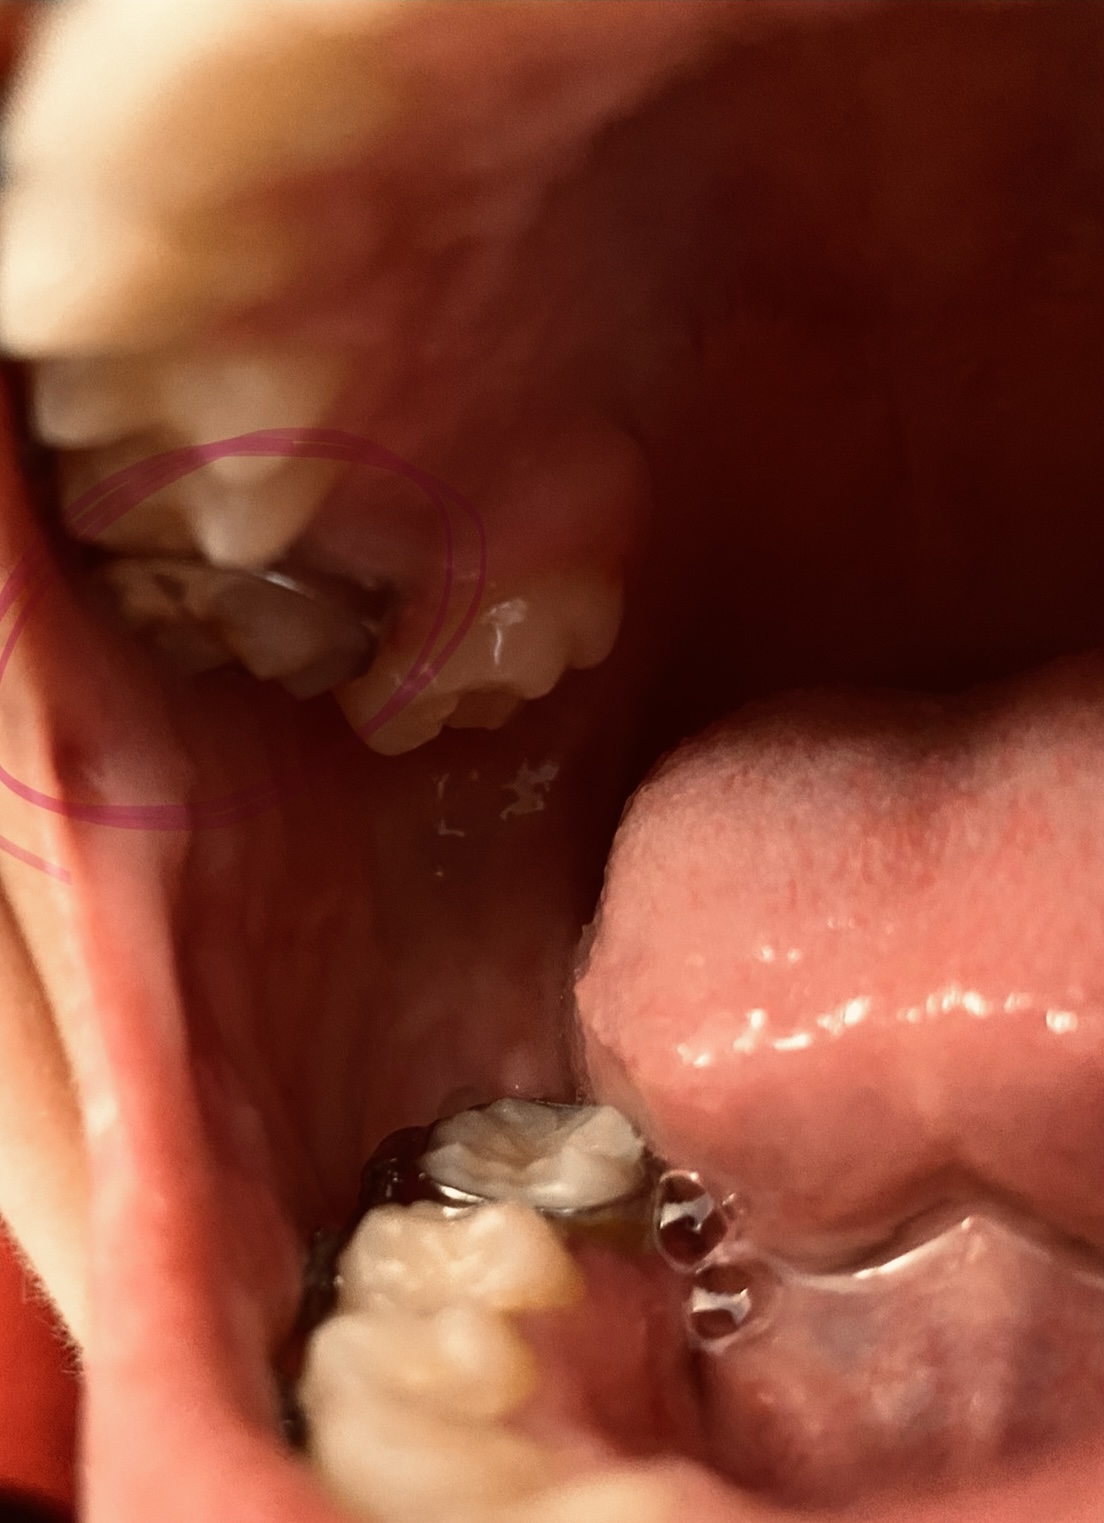

Hi I’ve been having issues with my jaws the feeling of them being extremely sore and I also cannot bite completely down on one of my sides of my mouth my teeth don’t look perfect or good they look “normal” I guess you can call it what would fix this ? Do I need braces ? My friends tell me I have a slight overbite but I can’t physically tell and I also bite the sides of my mouth and the inside of my lip a lot while eating.. what should I do ? I go to the dentist soon but is it best for me to go to a dentist or orthodontist?

From the picture submitted, it appears that you are biting edge to edge, which does need to be addressed and corrected by your orthodontist. It is ideal to mention these symptoms to your dentist at your check up appointment. Your jaw should not be sore on a regular basis. This could be a symptoms of a dysfunctional temporomandibular joint (TMJ). While the small spaces are more cosmetic, the uneven bite, soreness and inability to completely close on one side all raise red flags. Its best to correct these issues now, rather than to wait for them to worsen or for restorative treatment to be needed in addition to orthodontics due to wear patterns.